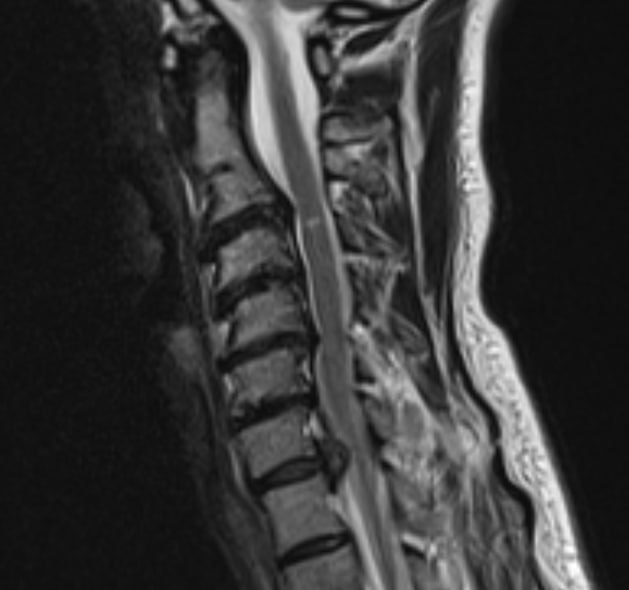

Сильная боль в шее, отдающая в левую руку, заставила обратиться в Долгопрудненскую больницу пациентку 45 лет. Целый месяц женщина испытывала мучения. Обследование на аппарате магнитно-резонансной томографии показало, что болевой синдром вызван крупной грыжей межпозвонкового диска.

💊 Поскольку время для лекарственной терапии было упущено, пациентка решилась на предложенную медиками операцию. Ей объяснили, что планируемое вмешательство будет малоинвазивным – то есть все действия врачи произведут через минимальный разрез с помощью микроинструментов, и восстановление не займёт много времени.

Мастерство заведующего отделением нейрохирургии Павла Савинкова и хирурга Данила Чёлушкина позволило выполнить операцию точно и аккуратно. Болевой синдром исчез сразу, а на следующий день счастливая пациентка уже отправилась из стационара домой.